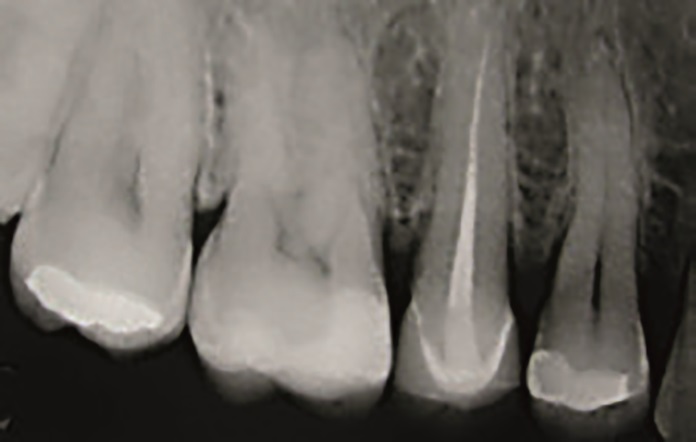

Obraz kliniczny po przeprowadzonym zabiegu i zdjęcie rentgenowskie przedstawiono na ryc. 22, 23, 24.